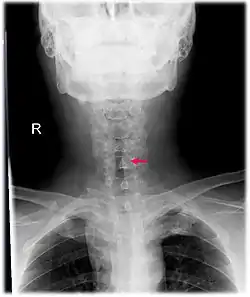

![]() صورة أمامية بالأشعة السينية على رقبة مريض به تضيق "تحت المزمار" ما بعد التنبيب. يمكن رؤية التضييق الحادث في تجويف القصبة الهوائية والمُشار إليه بالسهم. صورة أمامية بالأشعة السينية على رقبة مريض به تضيق "تحت المزمار" ما بعد التنبيب. يمكن رؤية التضييق الحادث في تجويف القصبة الهوائية والمُشار إليه بالسهم. | |